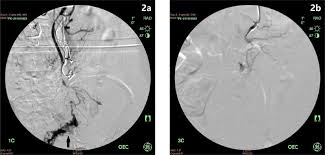

Https Mafiadoc Com Download Slow Flow Type Venous Malformation Of Tongue Semantic Scholar 5b9635db097c475e6c8b4579 Html

Https Mafiadoc Com Download Slow Flow Type Venous Malformation Of Tongue Semantic Scholar 5b9635db097c475e6c8b4579 Html from